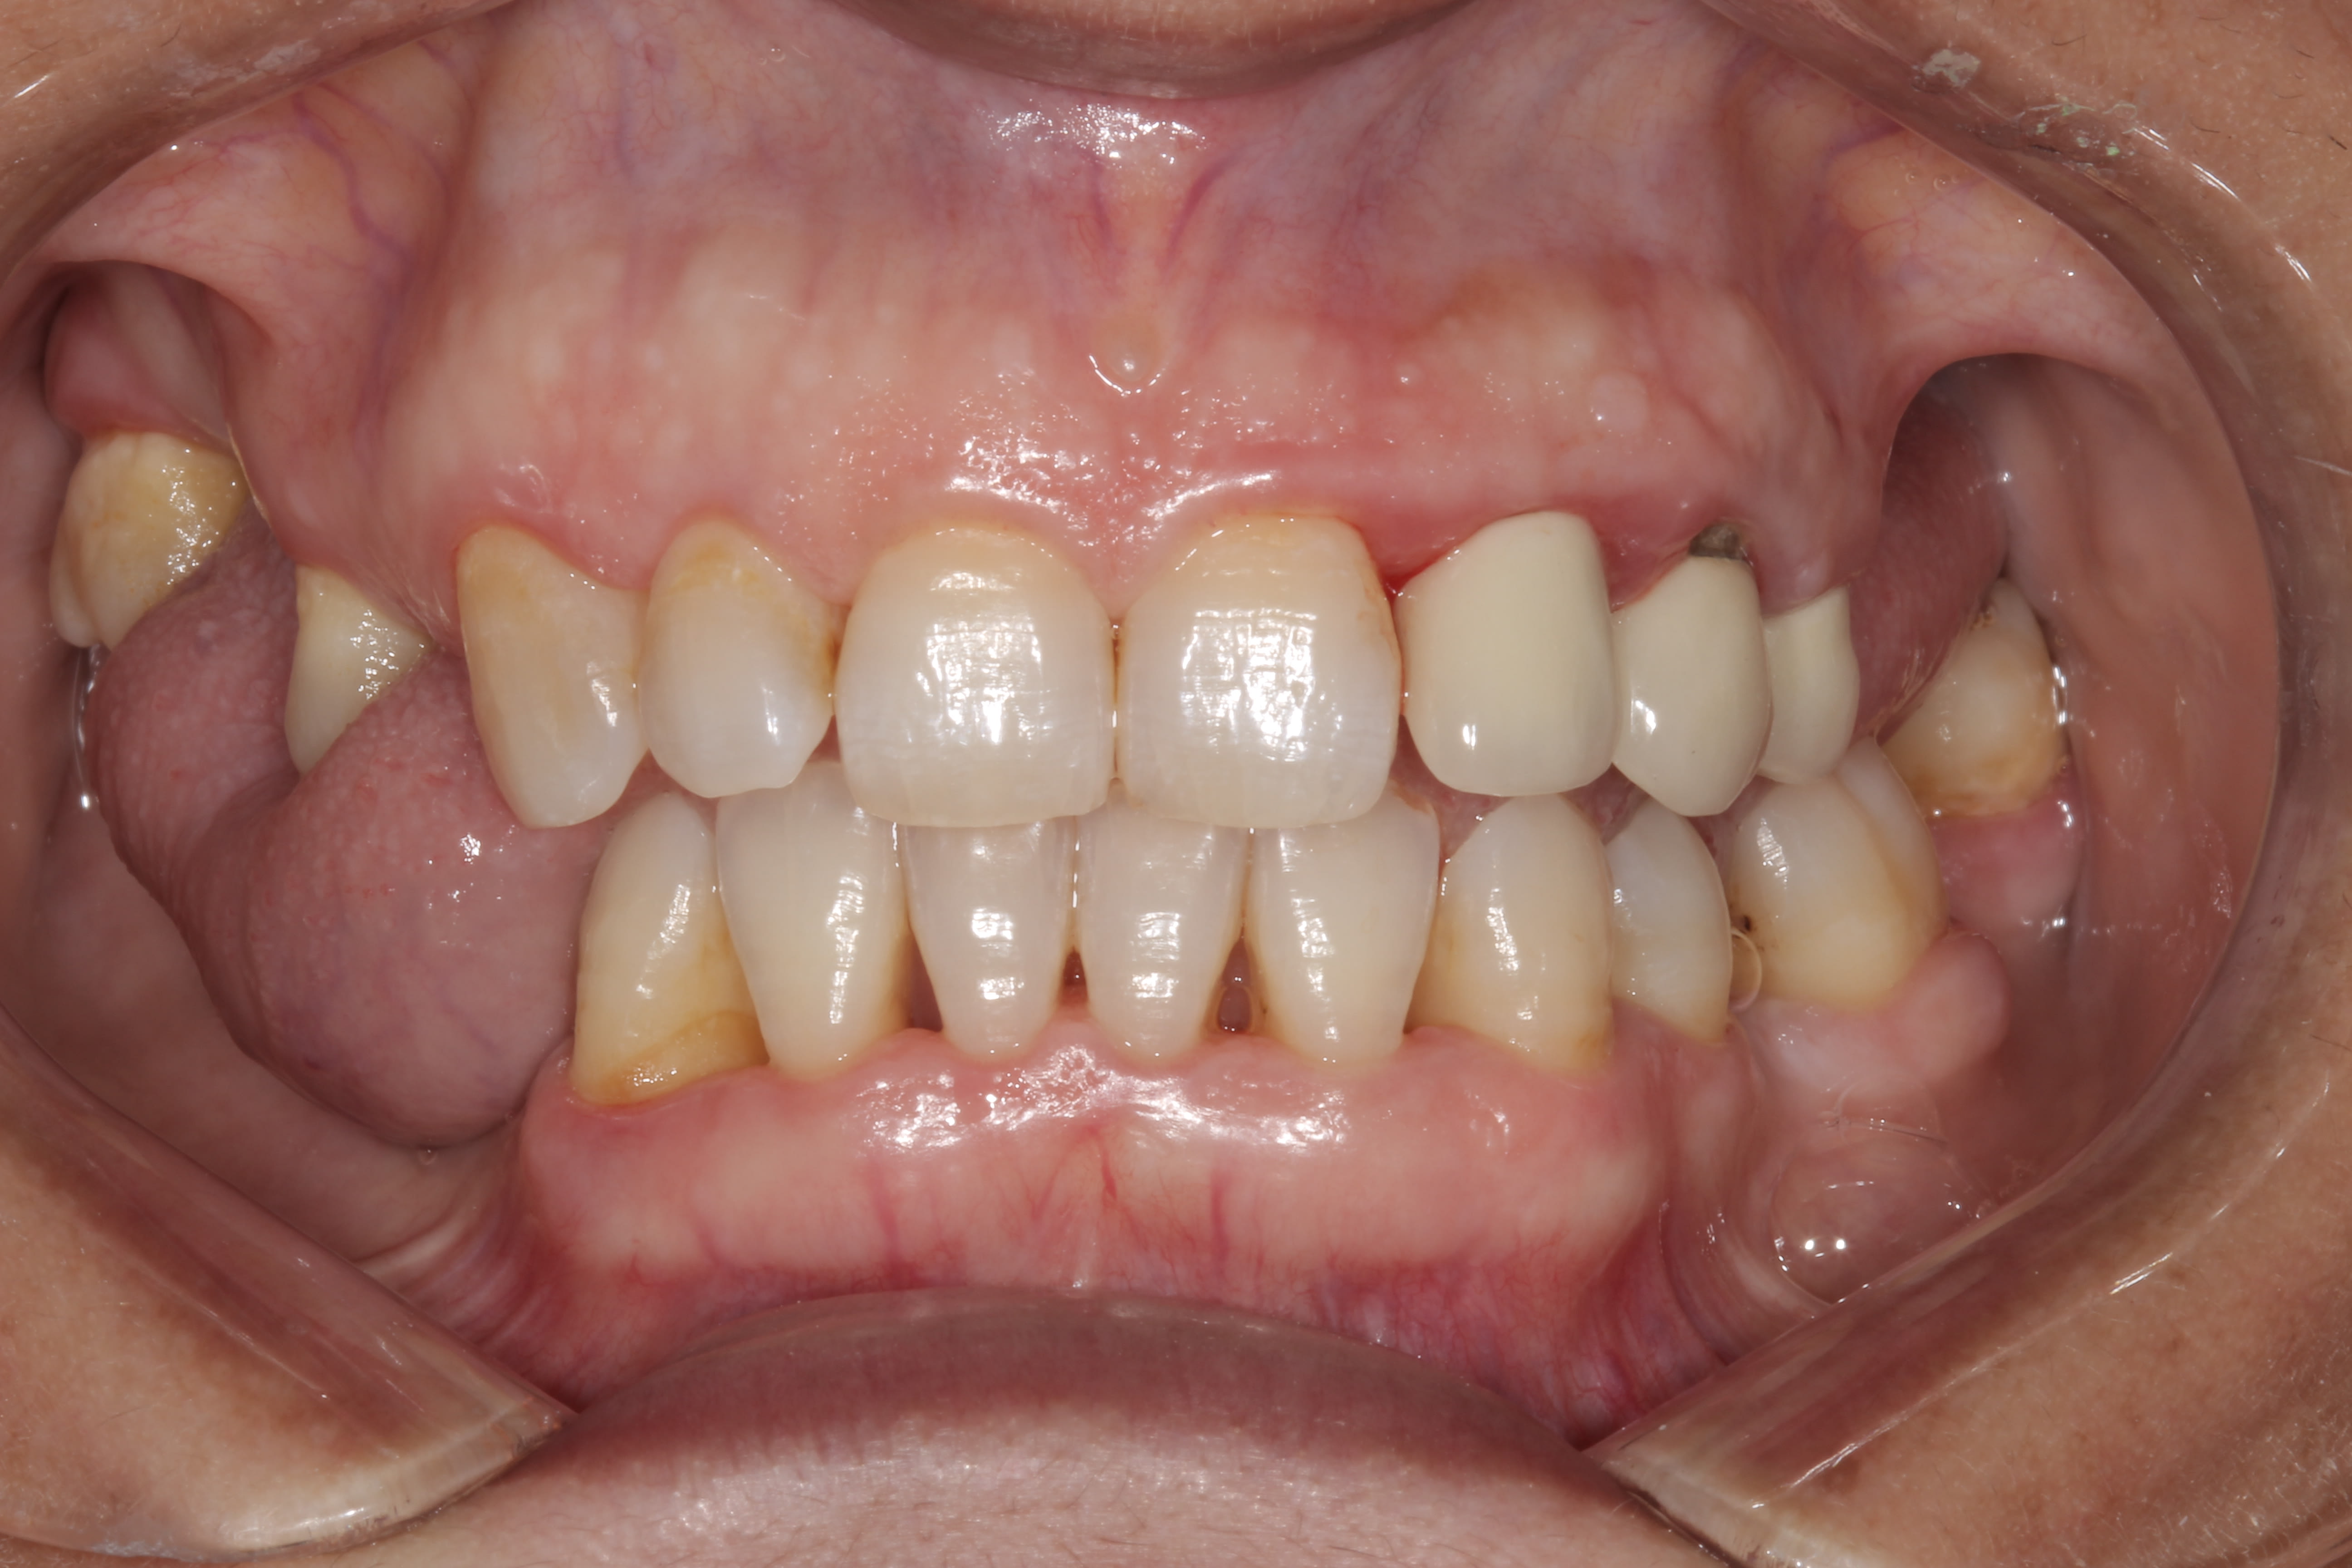

Voici Madame. le changement entre les deux photos c' est le surf et la motivation . Oui, oui, elle est au courant qu' elle doit ameliorer le brossage derriere, mais elle est motivée, passe les brossettes, avec des patients comme ca c' est un plaisir d' aller bosser, mais OK, c' est de loin pas le cas avec la plupart des patients.

1 2 hpmqzd - Eugenol

2 2 vmdus3 - Eugenol